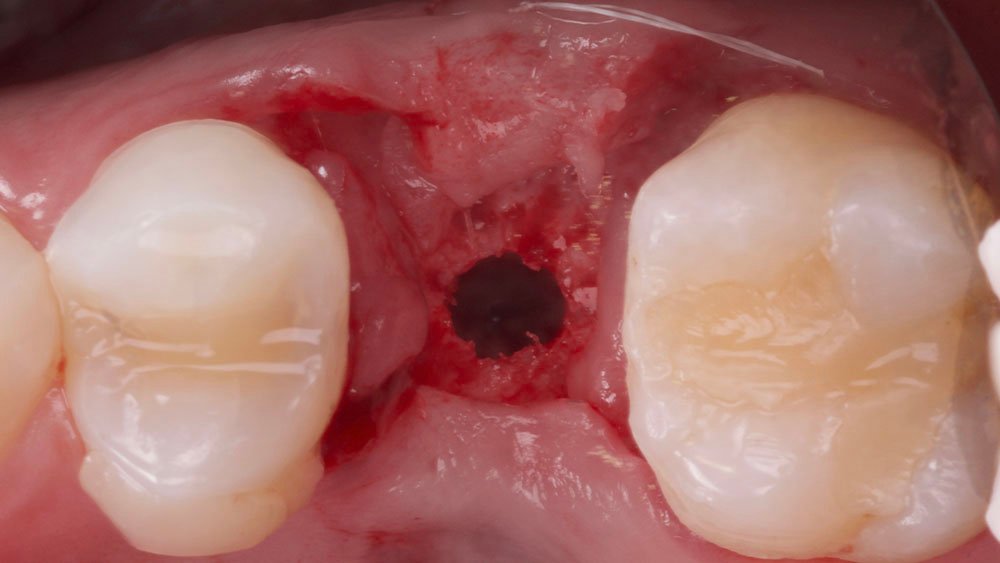

Os nervos alveolares superiores anterior, médio e o palatino maior foram anestesiados com dois tubetes de Cloridrato de Mepivacaína 2% (Cristália Produtos Químicos Farmacêuticos Ltda., São Paulo-Brasil). Com o auxílio de uma lâmina 15C (Syann Morton – Cód.11810 (HOS11810A)), foi realizada uma incisão ligeiramente palatinizada em retalho dividido, paralela ao tecido ósseo palatino, de modo a separar a porção mais epitelial do tecido conjuntivo palatino (aproximadamente 2 mm) da porção mais profunda (aproximadamente 3 mm), para que em seguida, uma segunda incisão no tecido palatino (abaixo do alçapão formado pela primeira incisão) pudesse liberar essa porção mais profunda (juntamente a periósteo) e a mesma seja rotacionada para a vestibular do defeito. Na sequência, outras duas incisões em retalho total (até periósteo) foram realizadas de modo a dar a forma das futuras papilas proximais. Uma última incisão superficial foi realizada na porção oclusal do defeito com a finalidade de desepitelização para que o tecido oclusal também fosse rotacionando para a vestibular. Para o descolamento do enxerto e mucosa vestibular foram utilizadas curetas Molt (Supremo Instrumentais).

Com auxílio de uma pinça porta agulha Castroviejo e pinça Dietrich 16 (Supremo Instrumentais), e fio de sutura Micro PTFE 5.0 (GolnitTM, Ucrânia-Europa – MICROSUTURE), foi realizado a sutura da região com pontos do tipo colchoeiro horizontal, posicionando o rolo dentro do retalho, tipo envelope na região vestibular.

Confeccionou-se um dente provisório aparafusado com coifa de titânio 4,5 x 4 mm – Linha Ideale (Implacil De Bortoli, São Paulo-Brasil), sobre o Pilar Ideale 4,5 x 4 x 2,5 (Implacil De Bortoli, São Paulo-Brasil), apoiado no Implante Maestro 4 x 11 (Implacil De Bortoli, São Paulo-Brasil), obtendo um torque aproximado de 40N. E por fim, realizou-se a proservação e acompanhamento radiográfico.